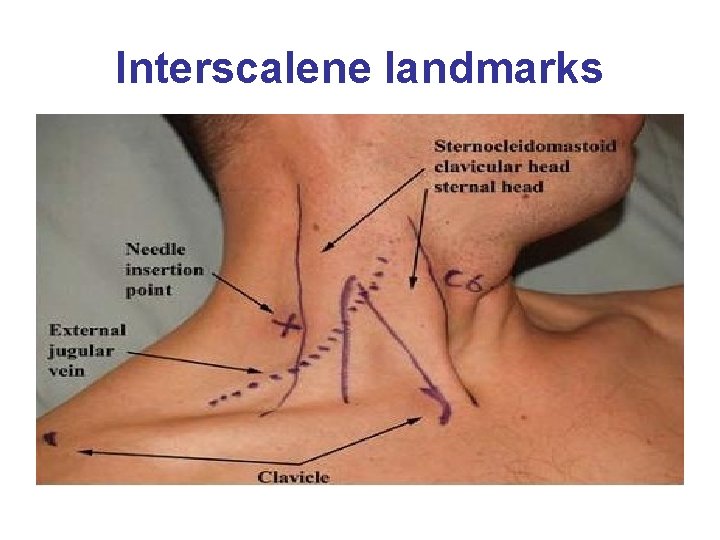

Interscalene Block • The approach to the brachial plexus lies in the neck between the interscalene muscle and the clavicle. • The patient lies supine with the head facing away from the side to be blocked. • Landmarks include the sternocleidomastoid muscle, external jugular vein, and the cricoid cartilage. The level of the cricoid cartilage corresponds to the C 6 vertebral body where the interscalene block is administered. • The needle is inserted into the interscalene groove in a slightly medial, caudal, and posterior direction to avoid the vertebral column and vascular structures. • Provides spread to the nonbrachial plexus Supraclavicular nerve which supplies sensory innervation to the cape of the shoulder. May not anesthetize the entire posterior aspect of the shoulder.

Interscalene landmarks